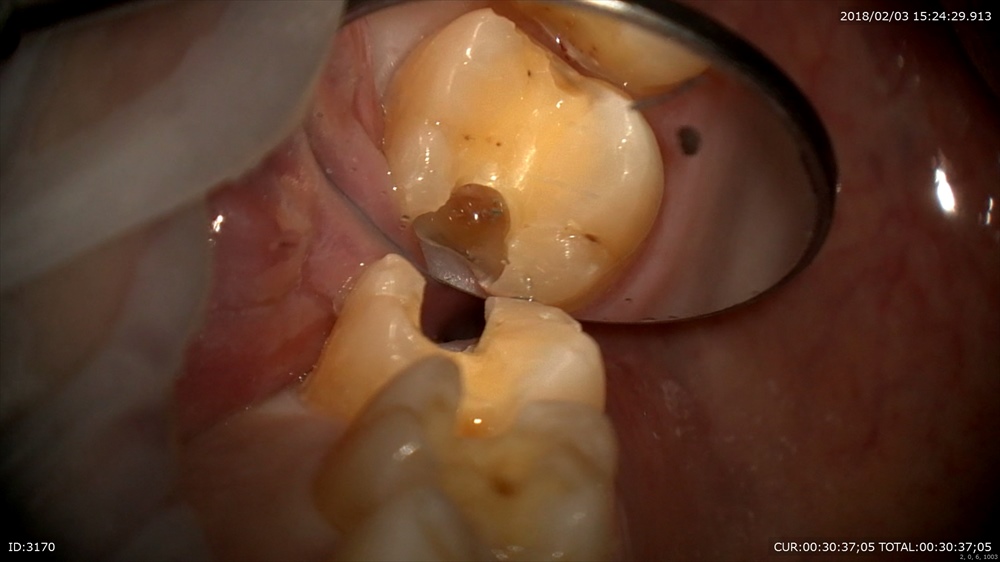

次も虫歯 歯に物がつまる。

これは。

われています。この様に虫歯は「力」によって起こることがあります。

クラック。ヒビがおきてそこから細菌の進入し

このように

大きな虫歯を内部で作ります。だからただ虫歯ができたら詰めるその行為では駄目で原因を探り力のコントロールを行います、そうでないと原因が断ち切れていないので同じ事がおきます。

深くても

MTAセメント

OK

型取りして次回で終了。